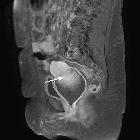

Radiographic features

CT

A heterogeneous mass as with ultrasound. Its relationship to other pelvic organs is delineated, in particular, to review for local invasion.

MRI

In the pelvis may add further to CT in delineated the tumor's relationship to adjacent organs and identifying lymph node disease.